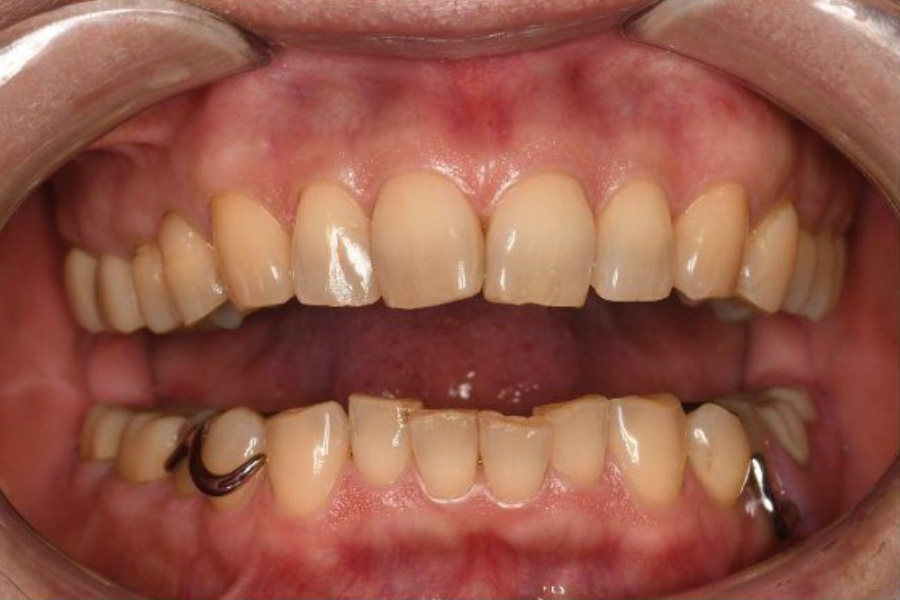

治療前

(口腔内写真)

【口腔内写真】左下奥歯の口腔内写真(側面)

歯の周囲には細菌の塊(プラーク)が停滞しており、その出す毒素によって土台となる歯ぐきが炎症を起こし、赤く腫れ上がっています。長年の過酷な「噛む力」対策としての削る調整を繰り返してきた影響で、歯そのものの高さ(歯冠長)が失われ、被せ物との継ぎ目(マージン)も露出してしまっています。

特に一番奥の被せ物には、強い衝撃による「ヒビ」や、根本が削れた部分に「大きな穴」が確認できます。これらは物理的な破壊であると同時に、細菌が歯の内部へ侵入するための「入り口」となってしまっている、非常に無防備な状態です。

【口腔内写真】正面から見たお口の状態

歯ぐきの表面には、過剰な圧力から歯を支えようとして地盤が肥大化した「骨隆起」がデコボコと隆起しています。また、頬の内側には頬圧痕(きょうあっこん)と呼ばれる白い筋が確認でき、これは就寝中だけでなく、日中も無意識に強い力で食いしばり(クレンチング)を続けている決定的な証拠です。

本来は尖っているはずの犬歯は鋭利さを失って平らにすり減り、前歯の表面には過酷な負荷による構造疲労で生じた「縦方向のヒビ(クラック)」が無数に入っています。これらはお口全体が設計限界を超えた「オーバーロード」の状態にあり、いつ致命的な破壊が起きてもおかしくない危険なサインです。